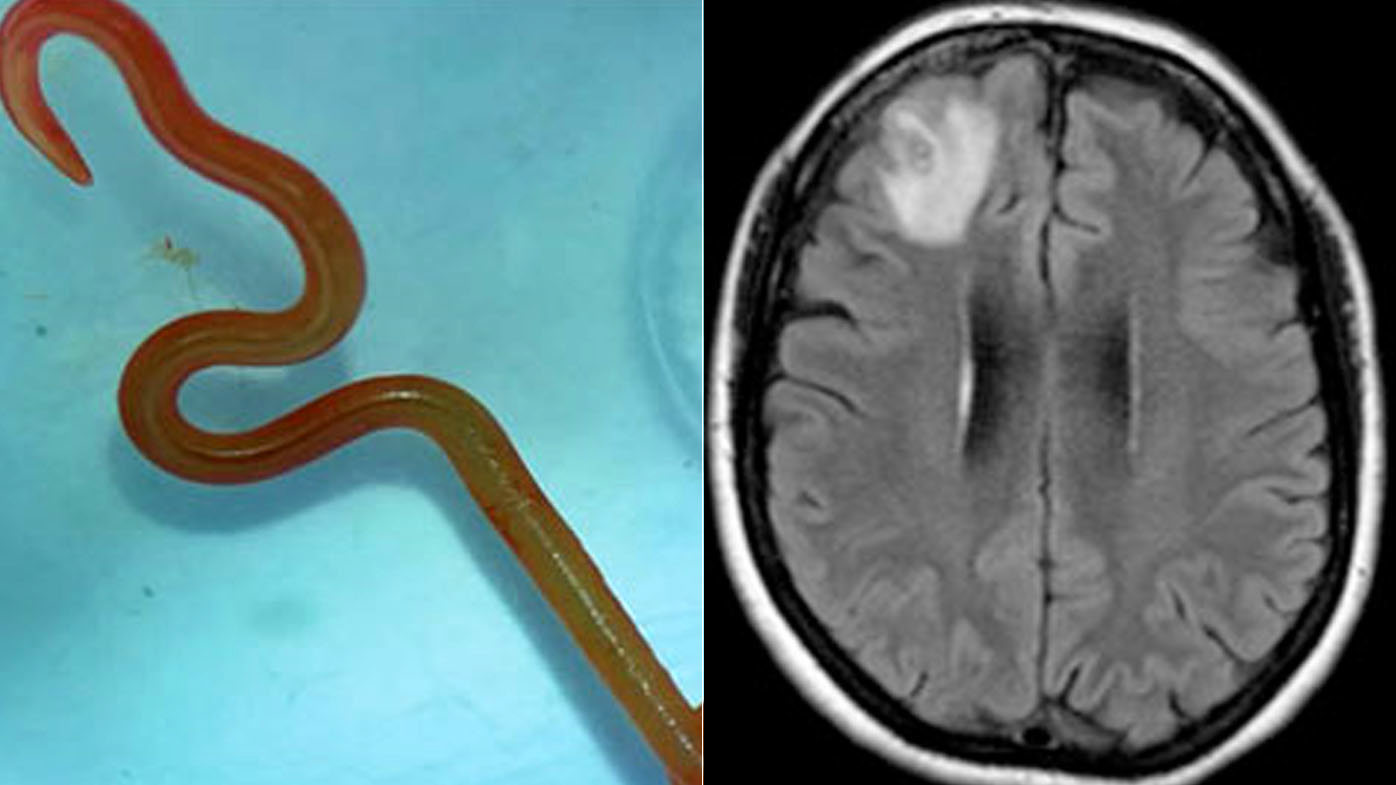

Australian medical experts found a live 8cms long roundworm from a python snake inside a NSW woman's brain, the first case of its kind in the world.

The Ophidascaris robertsi roundworm was pulled from the 64-year-old woman after brain surgery, still alive and wriggling.

The type of roundworm is commonly found in the carpet python snake.

The following year she began experiencing subtle changes in memory and thought processing and doctors advised her to undergo a brain MRI scan.

When the results came back, a neurosurgeon at Canberra Hospital was shocked to discover the live roundworm in the woman's brain.